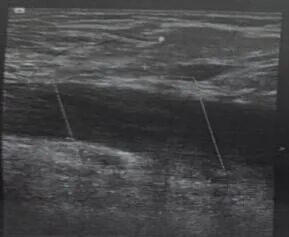

下肢超声检查

分娩住院时,下肢超声检查示左侧髂外静脉及股总静脉血栓形成,双侧下肢动脉及右侧下肢深静脉未见明显异常。